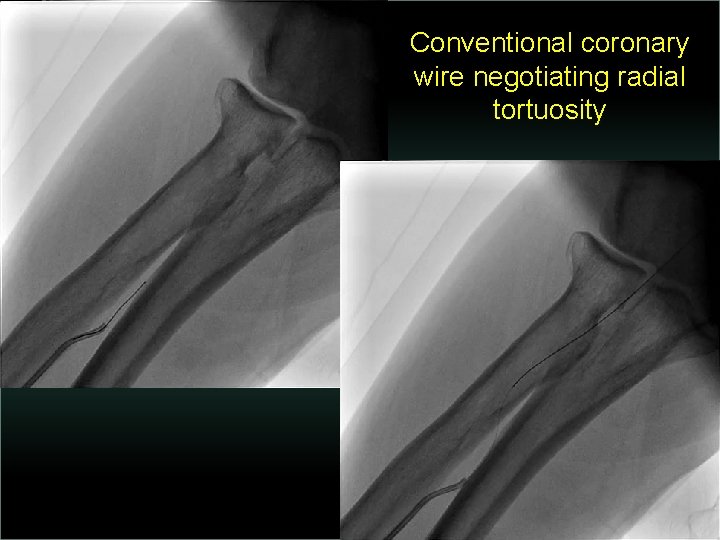

Transradial Interventions Difficult Anatomic Substrate Challenges and Solutions